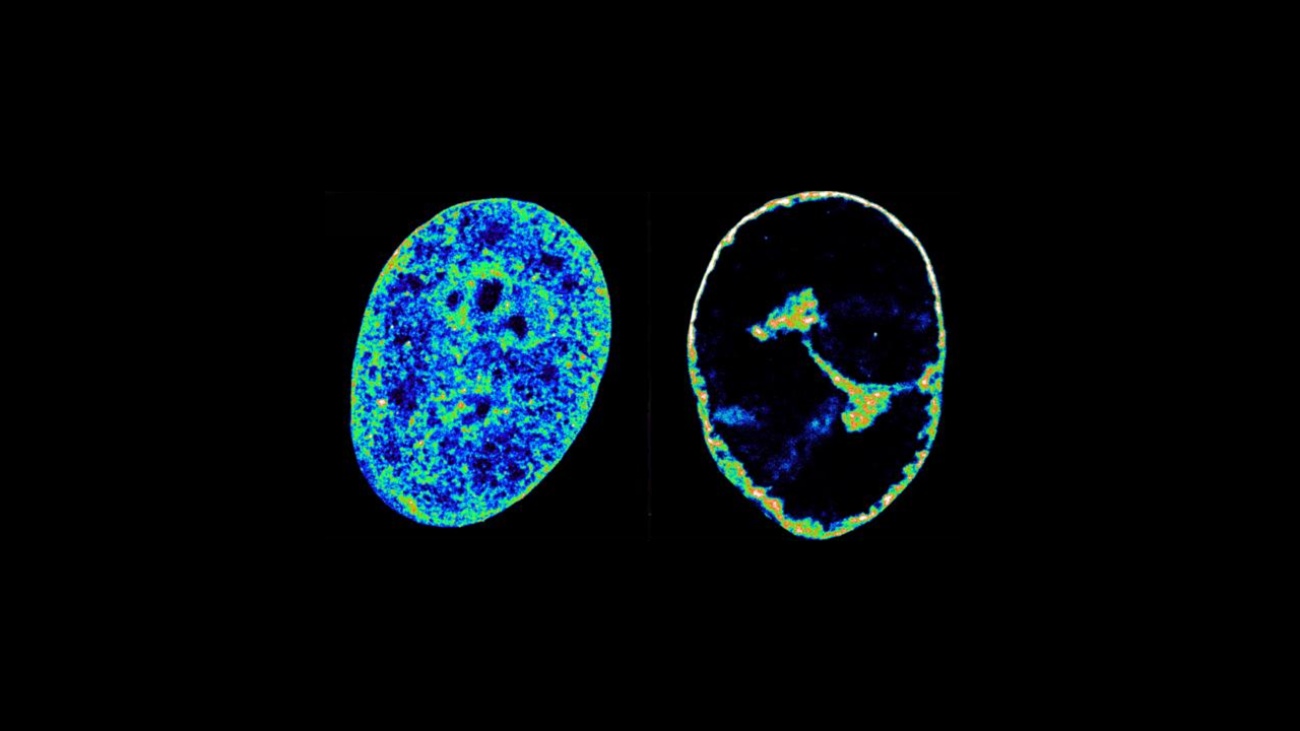

Links kun je zien hoe menselijk DNA er normaal uitziet in de cel, rechts kun je zien hoe die er uitziet na infectie met het herpesvirus. Beeld: Esther Gonzalez Almela and Álvaro Castells García.

Het herpes simplex virus (HSV-1) verandert de 3D-structuur van menselijk DNA opzettelijk, om zichzelf in zijn gastheer voort te kunnen planten.

Door deze diefstal stort de geïnfecteerde cel in. Die kan de twee gekaapte enzymen namelijk zelf amper meer gebruiken en daardoor lukt het niet om nog genoeg eiwitten te maken. Dat leidt er onder andere toe dat de rest van het DNA enorm strak wordt opgevouwen en nog maar 30 procent van zijn normale volume inneemt.